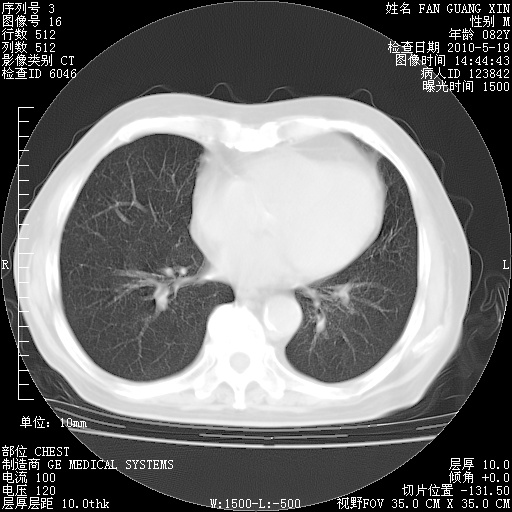

复查肺部CT,明显好转。为什么发热呢?

治疗3周后的肺部CT

治疗3周后的肺部CT纵隔窗